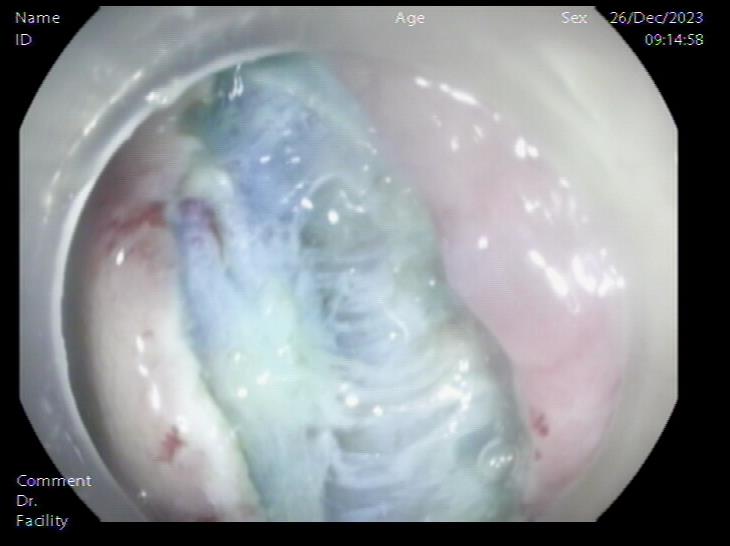

患者,66岁,女性,平素身体健康,以“发现胃肿物2年余”主诉入院,既往于外院行电子胃镜检查发现胃底隆起,直径约1.5-2.0cm,超声内镜检查考虑黏膜下来源间质瘤可能,不除外壁外病变压迫。外院CT提示胃底浆膜下囊性病变可能。患者及家属诊治心切,辗转数家医院后为求内镜下治疗遂来二附院。入院后在消化内科再次超声内镜检查,提示胃壁增生病变可能,增强CT提示胃底胃壁增厚,结合内镜检查。患者及家属强烈要求内镜下探查及病变切除术。术前在王进海主任的指导组织下,进行了专业组内及多学科讨论,与患者及家属充分沟通后,决定行内镜下切开探查及病变治疗术,必要时可行内镜-腹腔镜联合手术(LECS)。邹百仓教授带领内镜下肿瘤诊治及超级微创手术团队施行手术,术中逐层切开胃壁黏膜层及黏膜下层,暴露固有肌层,未发现胃壁病变,遂切开胃壁全层,局部腹腔探查,切口附近腹腔内似韧带组织上发现半球形隆起,表面透亮光滑,大小约1.5X1.5cm,术中请外科李军辉及袁庆攻教授会诊后确诊为囊性病变,讨论后建议可以观察或内镜切开引流,与患者家属沟通后家属强烈要求切开引流,遂用内镜切开刀切开囊肿,引流少量清亮囊液,囊肿塌瘪,观察囊肿切口及局部无出血,切除局部部分胃壁组织送检,内镜下严密关闭切口,留置胃管后,返回病房,常规对症治疗1周,患者无并发症发生,正常出院。

胃底SMT样隆起 内镜下切开刀行胃壁全层切开

腹腔内囊肿 腹腔内囊肿近景